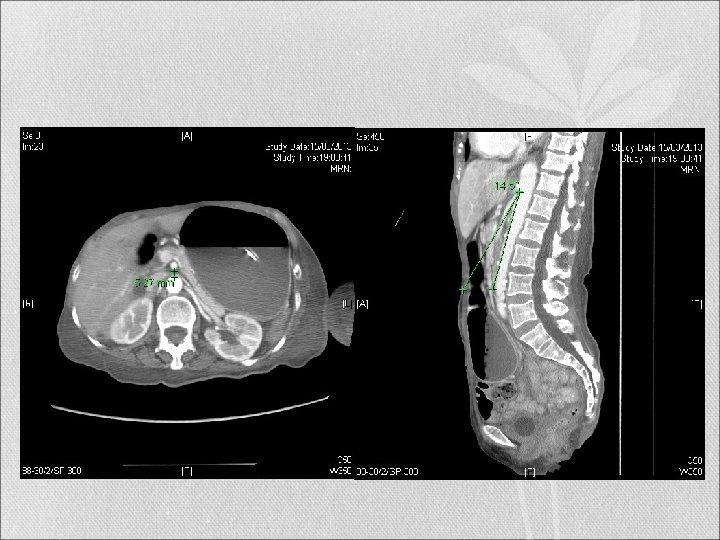

CT abdomen & Pelvis with Contrast

Radiographic Diagnostic Tools Computed tomography (CT) scan • can clearly demonstrate the aortomesenteric angle and distance accurately • the gastric and proximal duodenal dilatation, the duodenal obstruction (site of vascular compression of the duodenum) • local pathologies e. g. aneurysm or neoplasm, etc. • Provide an overall assessment of the abdominal cavity as well as the amount of retroperitoneal fat